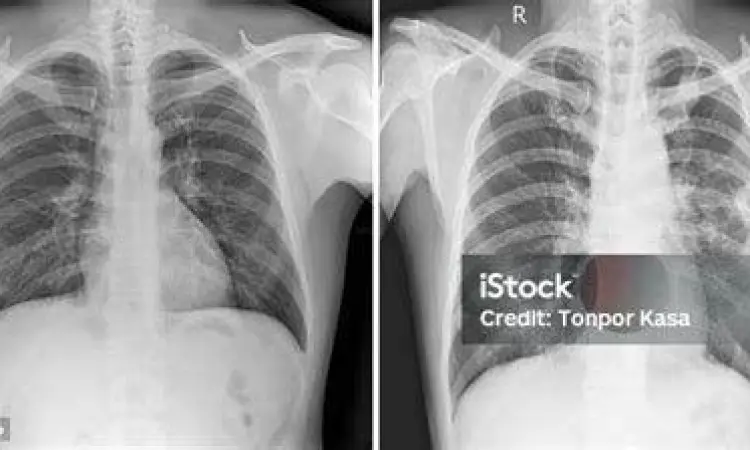

Interpretasi Gambar Paru-Paru Melalui Rontgen Dada

Dalam dunia medis, gambar paru paru sering kali diperoleh melalui teknik pencitraan rontgen dada (Chest X-Ray) atau CT Scan. Gambar rontgen menunjukkan kepadatan jaringan di dalam rongga dada. Udara di dalam paru-paru akan tampak berwarna hitam (radiolusen), sedangkan jaringan padat seperti tulang rusuk atau jantung akan tampak berwarna putih (radiopak).

Seorang radiolog akan mencari tanda-tanda abnormalitas seperti infiltrat (bercak putih) yang bisa mengindikasikan infeksi paru atau pneumonia. Selain itu, jika terdapat cairan di antara lapisan pleura (efusi pleura), gambaran rontgen akan menunjukkan sudut kostofrenikus yang tumpul, bukan lancip seperti pada kondisi normal. Memahami gambaran rontgen ini sangat membantu dokter dalam mendiagnosis penyakit secara akurat dan cepat.

- Pneumonia: Tampak sebagai area konsolidasi atau bercak putih yang tidak merata.

- TBC (Tuberkulosis): Sering menunjukkan kavitas atau lubang pada bagian atas paru-paru.

- Edema Paru: Menunjukkan adanya penumpukan cairan yang membuat gambaran paru terlihat "berkabut".

- Pneumotoraks: Tampak sebagai area hitam tanpa corak vaskular, menandakan adanya udara yang terjebak di rongga pleura.